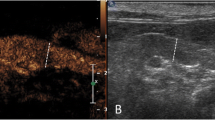

Contrast-enhanced ultrasound displayed a perfusion of the splenic tissue characterized by an early wash-in phase with a rapid enhancement of the small splenic arteries, 10 ± 2 s. (mean ± SD, standard deviation), a heterogeneous phase of enhancement of the spleen that became homogeneous at a mean peak enhancement of 45 ± 15 s. (SD), and a slow decrease of enhancement in the wash-out phase (Fig. 1). The absence of splenic lesions was confirmed by CEUS.

All the dogs were subjected to B-mode ultrasonography, Doppler ultrasonography and CEUS. Ultrasound and Doppler examination were performed by the same investigator (FM) using a scanner Mindray M9 (Shenzhen, China), equipped with a linear probe (10-12-MHz). The dogs were not sedated and were manually restrained in right lateral recumbency, the hair was clipped, and alcohol (70 %) and coupling gel were applied to the skin.

CEUS examination was carried out using a linear transducer probe (10-12-MHz) with contrast agent capability. The contrast agent, INN-sulphur hexafluoride (SonoVue®, Bracco International, Milan, Italy), was prepared following the manufacturer’s recommendations and was quickly injected (0.05 mL/kg body weight) via a three-way stopcock and an 18-gauge catheter placed in the cephalic vein, according to a previously reported methodology [33, 34]. Each dog received two bolus injections of contrast agent, which were standardized and administered by the same investigator (SD). The first bolus was administered to assess the kidney while the second bolus, injected approximately 5–10 min after the first bolus, was used for the assessment of the spleen. The contrast injection was immediately followed by a 5 mL saline flush, as previously described [10].

Injection of the contrast agent and activation of a timer were started simultaneously and video clips were recorded for 2 min. Since the animals were not sedated, care was taken to keep the probe in the same position for at least 2 min. The spleen was observed with a mechanical index set at a low value (0.09). A single focal zone was placed in the deepest part of the spleen. The overall gain and time-gain compensation have been set so that no signal is obtained from the underlying splenic parenchyma. To identify the splenic capsule as an anatomic reference, its background signal was maintained.